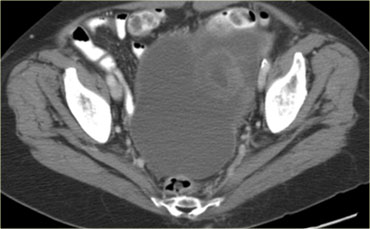

Hình CT cho thấy các khối nang phức tạp ở cả hai buồng trứng.

Mặc dù ung thư biểu mô tuyến nang thanh dịch có thể xuất hiện hai bên, nhưng loại này thường có dạng đơn thùy hơn là đa thùy.

Hầu như không nhìn thấy một phần của ung thư đại trực tràng dạng vòng nhẫn (mũi tên xanh).

Nhìn thấy rõ ràng là các tổn thương cấy ghép dạng nang trên phúc mạc phản chiếu (mũi tên đỏ).

Đây là các tổn thương di căn buồng trứng dạng nang của ung thư đại trực tràng.